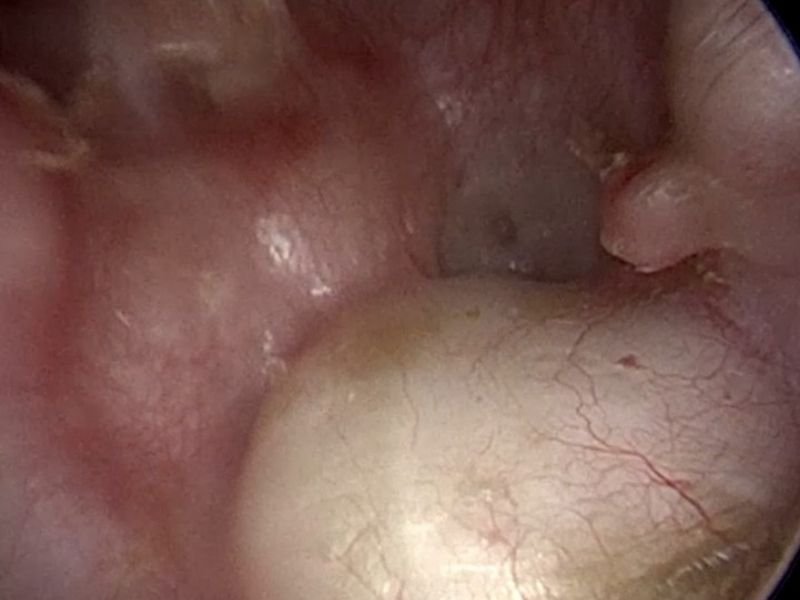

O que é a perfuração do tímpano?

O tímpano, também conhecido como membrana timpânica, é uma fina estrutura que separa o ouvido externo do ouvido médio. Ele desempenha um papel vital na audição, convertendo ondas sonoras em vibrações que são transmitidas para os ossículos do ouvido médio. Quando essa membrana é danificada por trauma, infecções ou outros fatores, o paciente pode experimentar:

A perfuração pode variar em gravidade e sintomas, dependendo do tamanho e da localização da lesão.